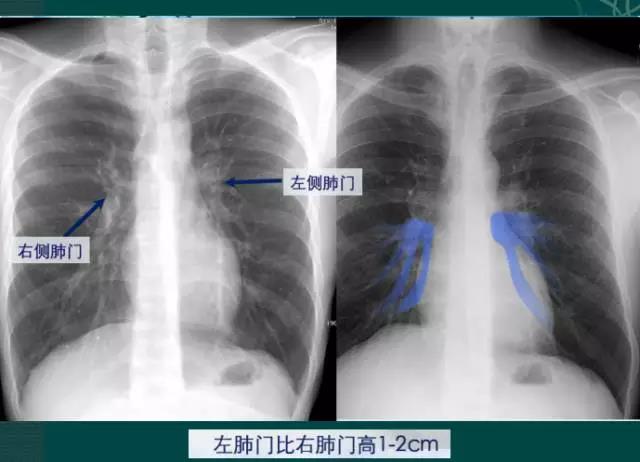

右肺门可分为上、下两部。上部约占1/3,由上肺静脉、上肺动脉及下肺动脉后回归支构成。上肺静脉下后干构成右上肺门的外缘;右肺门下部 约占2/3,由右下肺动脉干构成,其正常宽度不超过15mm,沿中间段支气管外缘平行向外下走行。右肺门上、下部相交形成一钝的夹角,称肺门角,正常该角顶清晰。如下图

左肺门亦分为上、下两部。上部由左肺动脉及其分支、左上叶支气管和左上肺静脉及其分支构成;下部由左下肺动脉及其分支构成,常被心影所遮盖。